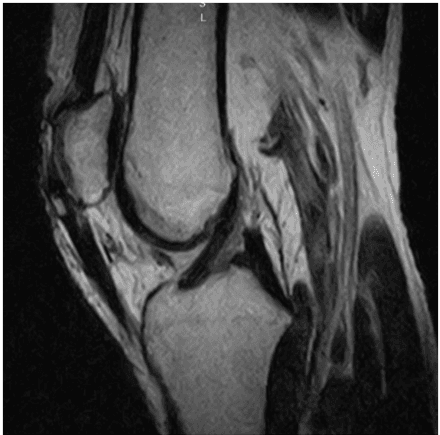

The effect of autologous adipose derived mesenchymal stem cell therapy on juvenile osteochondritis dissecans of the patella: a case study

Alessandro Russo, Vito Coco, Stefano Zaffagnini, Journal of Surgical Case Reports, 2020